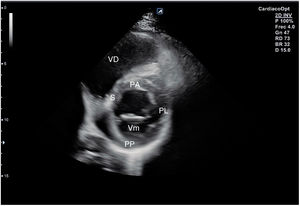

Desde el plano anterior, sin cambiar el apoyo de la sonda, se realiza un giro de 90° en sentido horario, obteniendo el plano paraesternal de eje corto, que es un corte perpendicular al anterior (fig. 4). En este eje, basculando la sonda, se puede cortar de forma transversal el corazón desde el ápex, si se angula hacia la cadera izquierda, pasando por los músculos papilares (fig. 5) hasta la base, donde están la válvula mitral (fig. 6) y aórtica (fig. 7), si se hace hacia el hombro derecho.

En este plano se visualizan todas las paredes del VI. A nivel de la válvula mitral se observa el orificio valvular, sus valvas con las comisuras, el tabique interventricular y las paredes libres de ambos ventrículos.